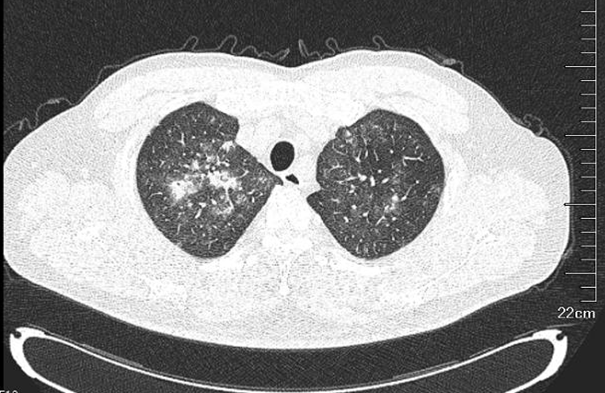

为进一步排查发热原因,寻找潜在感染灶,予胸腹盆部增强CT,结果提示:两肺感染,两肺上叶为著,较前稍进展;甲状腺左叶结节灶;脂肪肝,肝囊肿;肝左外叶稍低密度灶:不典型血管瘤?其他?双侧肾上腺结节样增生;左侧肾盂旁囊肿可能,左肾微小结石;前列腺钙化。心脏彩超:左室壁部分心内膜面及部分乳头肌回声增强,心包少量积液,三尖瓣轻度反流(图2,图3)

图2  胸部CT两肺感染,两肺上叶为著,较前稍进展

图3  腹部增强CT肝左外叶稍低密度灶